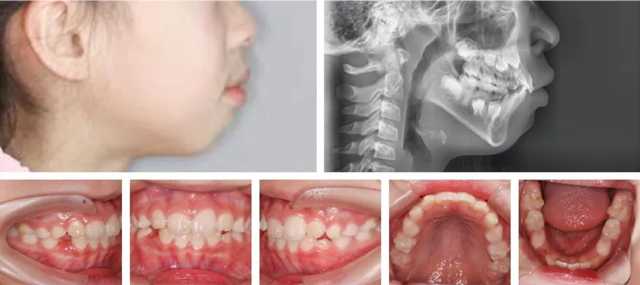

结合口内牙齿、面型、牙片综合评估,孙叡医生制定了一份详尽的矫正方案:扩弓排齐牙齿,解除侧切牙的拥挤状况,给后续恒牙萌出留出位置,并适量内收上颌前牙改善外观。同时还要进行唇肌功能训练,以改善口呼吸的习惯。

矫正半年后

经过半年的矫正,家长对朵朵牙齿的整齐效果非常满意。孙叡医生强调,早期矫正并不是简单的纠正牙齿问题,而是引导颌骨正常生长发育,因此建议更多家长能像朵朵妈妈一样,多关注孩子牙齿萌出、生长以及颌面发育的情况,如发现问题可及时到专业口腔机构就诊。